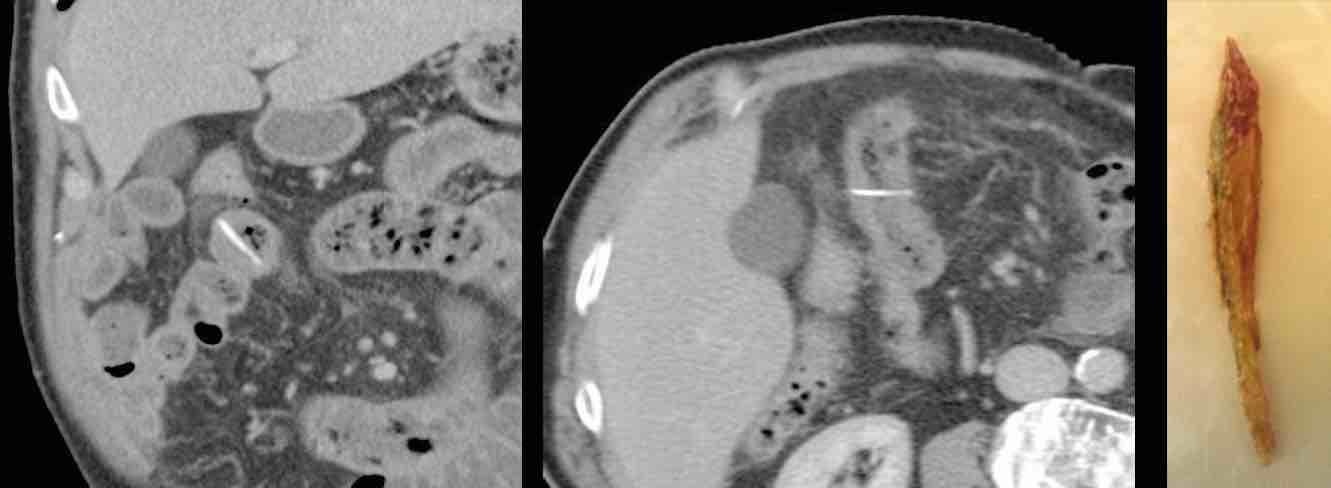

Bệnh nhân này nhập viện với đau bụng trên và CRP 245. Siêu âm và CT phát hiện một dị vật thẳng, hơi tăng tỷ trọng, có thể là tăm cocktail (đầu mũi tên).

Trong phẫu thuật hai ngày sau, áp xe gan đã được dẫn lưu, nhưng không tìm thấy dị vật. Sau đó bệnh nhân đáp ứng tốt với kháng sinh.

Vào ngày thứ 15, CT cho thấy áp xe đang thoái triển với dị vật (đầu mũi tên) vẫn còn tại chỗ. Cuối cùng, bệnh nhân hồi phục với liệu trình kháng sinh dài ngày.

Bệnh nhân nam 75 tuổi với nghi ngờ lâm sàng áp xe cơ thắt lưng chậu.

CT xác nhận áp xe và xác định một dị vật sắc nhọn thẳng, hơi tăng tỷ trọng, có vẻ đã di chuyển từ ruột non vào cơ chậu.

Hình dạng và tỷ trọng gợi ý đây là que gỗ hơn là xương cá.

Bằng phẫu thuật xâm lấn tối thiểu, cả mủ và que gỗ đều được lấy ra.

Bệnh nhân có hàm răng giả, tiền sử cắt ruột thừa và có thói quen “gạt” thịt khỏi que xiên bằng nĩa.